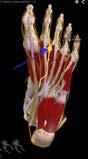

Missempfindungen, Kribbeln, Brennen oder stechender Schmerz: Bei einer Polyneuropathie sind periphere Nerven geschädigt. Das können zum Beispiel Nerven in den Armen und Beinen sein oder solche, die innere Organe versorgen. Zu den häufigsten Ursachen dieser Nervenschädigung gehören Diabetes mellitus. Rechtzeitig behandelt lassen sich die Schäden eindämmen.

Normalerweise fließen Nervensignale vom Gehirn ohne Probleme bis in die Füße und zurück. Informationen von Berührungsreizen, dem Druck-, Temperatur- oder Schmerzempfinden sowie von Vibrationen werden an das Gehirn weitergegeben. Damit diese Kommunikation funktioniert, brauchen die Nerven Nährstoffe. Bei einer Polyneuropathie ist der Stoffwechsel aber nachhaltig gestört. Ohne ausreichend Nährstoffe werden die Signale nicht mehr in die Extremitäten übertragen. Die Auswirkungen sind unterschiedlich. Sind Nerven geschädigt, die die Muskeln versorgen, spüren Betroffene Muskelschwäche, feinmotorische Bewegungen fallen schwer. Sind dagegen die für das Gefühl verantwortlichen Anteile verschiedenster Nerven geschädigt, entstehen Empfindungsstörungen, ein Kribbeln oder ein taubes, pelziges Gefühl.

Besonders empfindlich und anfällig für Schäden sind die langen Nervenbahnen, die bis in die Füße und Zehen reichen.

Die Zehen sind daher häufig als Erstes betroffen. Sind die Beine betroffen, können sich Koordinationsprobleme beim Gehen entwickeln. Ist das Temperaturoder Schmerzempfinden gestört, kann es leicht zu Verletzungen kommen – beispielsweise Verbrennungen. In schweren Fällen kann das sogenannte autonome Nervensystem angegriffen sein. Es steuert die Funktion der inneren Organe. Daher reichen Beschwerden von einer gestörten Funktion des Magen-DarmTrakts, des Herz-Kreislauf-Systems und der Harnwege.